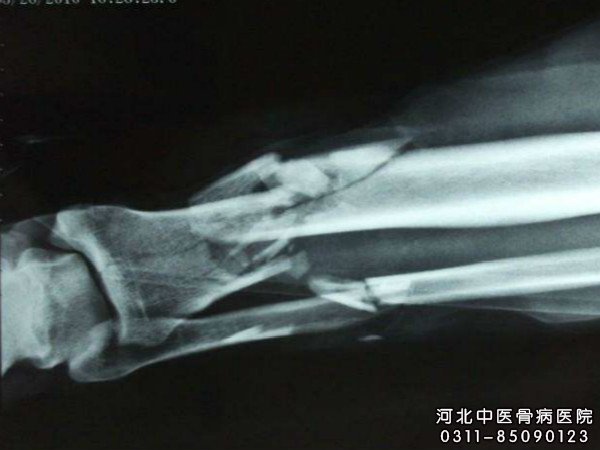

由于炎症反复发作,多处窦道,对肢体功能影响较大,有肌肉萎缩;如发生病理骨折,可有肢体短缩或成角畸形;如发病接近关节,多有关节挛缩或僵硬。X线照片可显示死骨及大量较致密的新骨形成,有时有空腔。X线照片显示长骨干骺端有圆形稀疏区,脓肿周围骨质致密加重,这是骨髓炎症状表现之一。